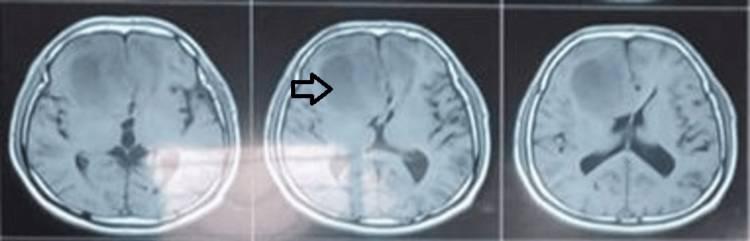

常规术前血液检查在正常范围内,胸部X光检查未发现任何明显异常。大脑的磁共振成像(MRI)发现右额叶存在轴内占位性病变,对左侧胼胝体产生压迫,伴大脑镰下疝。在T1加权图像上,病变表现为等强度(图1),在T2加权图像上表现为高强度(图2),并显示均匀的扩散限制。

图2 术前MRI脑(T2图像);右额叶轴内高强度占位性病变